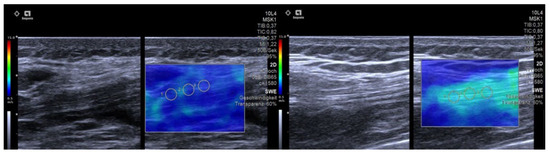

2.2. Ultrasound-Based Shear Wave Elastography